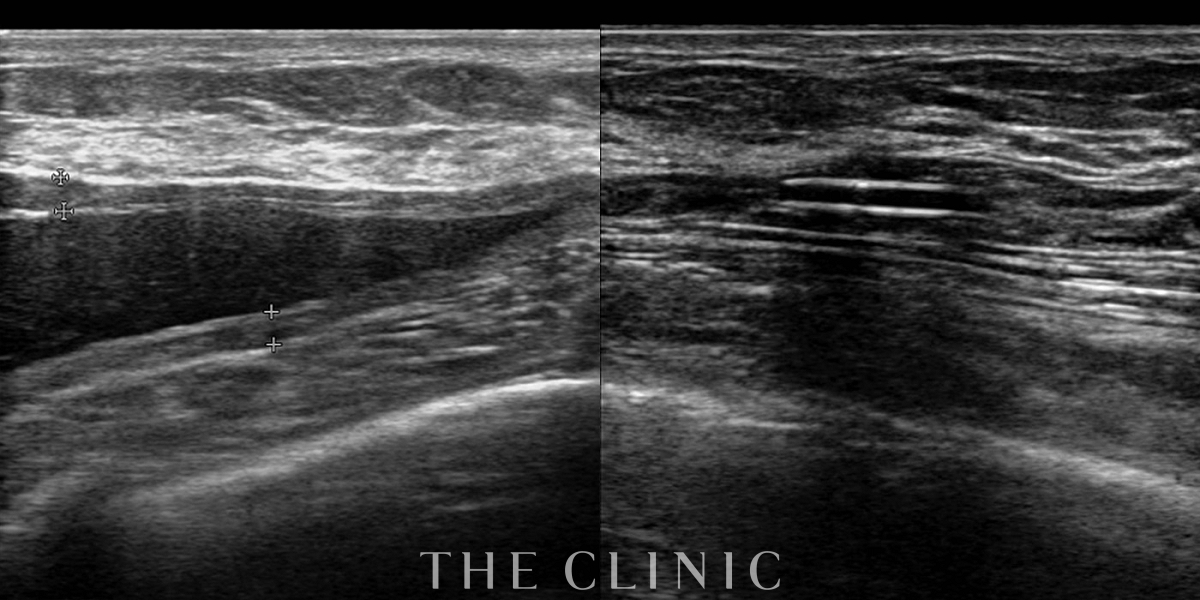

コンデンスリッチ豊胸を行うために、前もってアクアフィリングの除去を行いました。エコーで確認するとかなり厚い被膜が形成されています。

アクアフィリングは生理食塩水で溶解されるとのことで、エコー下に生理食塩水を注入しましたが、なかなか溶解できず、ヒアルロニダーゼも追加してなんとか溶解除去することができました。右側は炎症があった為か、汚く濁った状態でした。